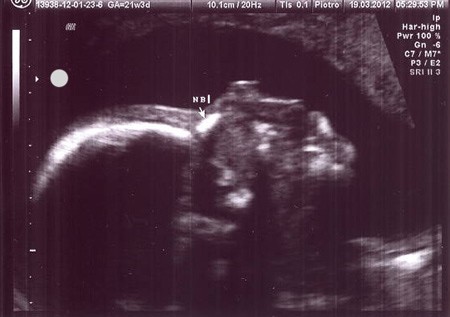

To i ja się pochwalę :zawstydzona/y:. Zdjęcia z 21 tygodnia i 4 dnia.

1a.jpg

2a.jpg

Siusiaka nie pokażę, bo może by się wstydził kiedyś :-D.

Witam. Więc i ja sie pochwalę wczorajszym usg ( miałam drugie prenatalne)

W skrócie wszystko ok, waży aż 417g. (21 tydzień i 4 dzień)

Obraz 001.jpg pod koniec w opisie mam zapis- Płeć- prawidłowe męskie narządy płciowe :tak:

więc potwierdzony ogonek po raz czwarty, mogę robić zakupy :-)